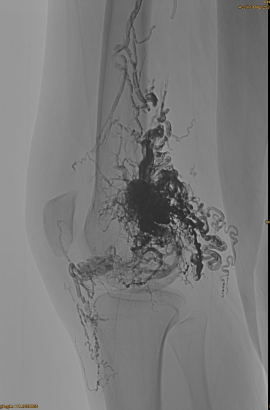

Informações básicas do paciente: mulher, 36 anos; AVM Pelvis, quadril, joelho, OSG esquerdo, múltiplas embolizações pre -.

DSA inicial:

Resultado final:

Quase nenhuma saída venosa:

Fase tardia, outro embaraço necessário, mas muito melhor: